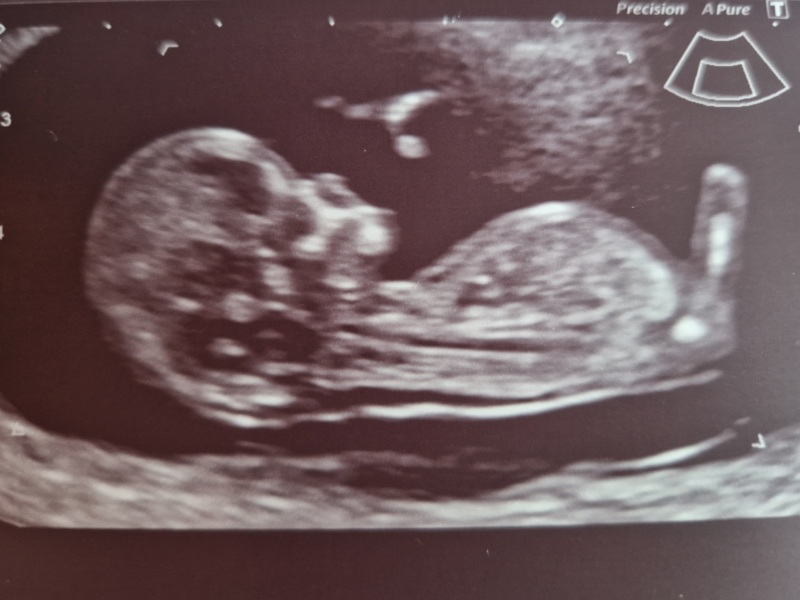

1yearplan · 21/05/2024 12:46

Hi everyone, I hope you're all keeping well. I had my 16 week appointment today and got to hear my daughter's heartbeat, so that was lovely. I've got a 16 week detailed scan on Thursday, so I'm hoping once that is complete and all being well, I might be able to start to enjoy this pregnancy rather than worry.

had my screening scan yesterday all good, 20 wk scan booked for July when i'll be 20+4 so excited for that! still fairly tired but otherwise thankful to feel ok 😊

1yearplan · 22/05/2024 11:19

That's great @Cazzy87 I've got mine tomorrow. I'm looking forward to seeing my baby girl again, but nervous about it too.

Had my 12 week scan last week and just got my screening results through, all low which I was surprised at due to being 40 this time around, so definitely a relief. Now have a new due date of 25th November and already have 20 week scan date.